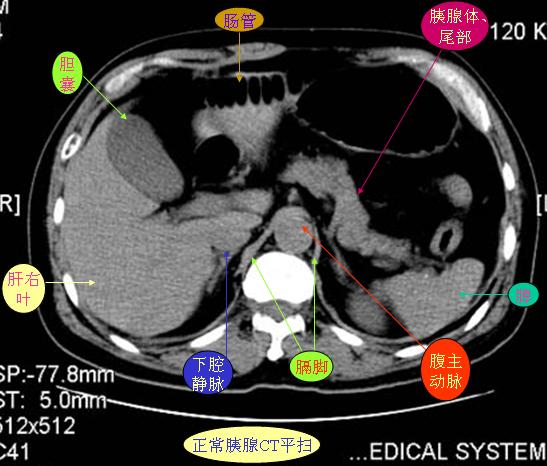

腹部ct解剖与基本病变